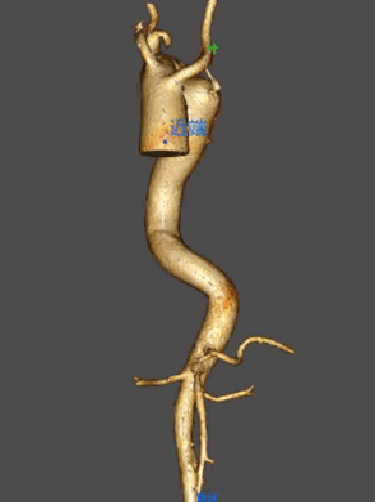

★Case 1 主动脉夹层+ALVA

治疗难点:弓上分支变异,夹层病变累及LSA,迷走左椎动脉

手术策略:

单分支

支架近端定位于LCCA

分支前缘预开窗(迷走左椎动脉)

结果:成功封堵破口,各分支通畅,左椎动脉保留